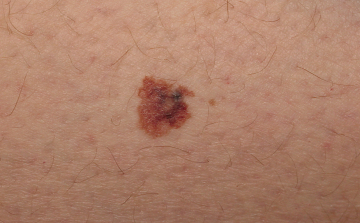

A melanóma növekedését \'ösztönző\' génmutációkat fedeztek fel